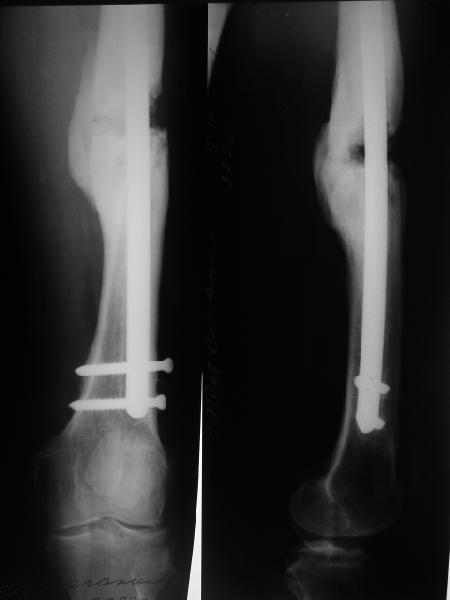

Возможно, проф. Лазарев предложит другой вариант, а в наших условиях мы бы закрыто заштифтовали бы бедро антеградно. Устранили бы варус, используя голень как рычаг, вероятнее всего, даже дистрактор не понадобился бы. В приницпе, можно и ретроградно ири наличии движений в колене, но варус будет труднее устранить - можно и предварительно аппаратом в таком случае.

Стержень можно использовать и обычный потолще, но лучше бы с возможностью введения большего, чем два фронтальных, числа запирающих винтов.

Учитывая наличие этой мощной спайки, запереть можно сразу динамически.

Рефрактур уж точно можно будет не опасаться, а за несколько месяцев даже при отсутствии заполнения костью по всей окружности, этот обходной "мостик" упрочнится и возьмет на себя нагрузку. В приложении пример такого рода "эндопротезирования диафиза", прошло больше 3 лет.